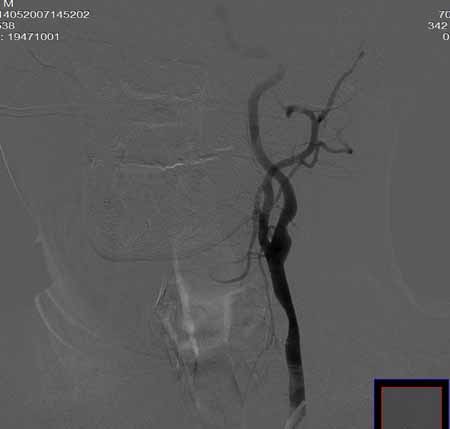

男,60岁。

腹主动脉、颈总动脉、颈内动脉狭窄支架置入术,最少放了三个支架吧,得十几万吧。

颈总动脉支架置入术。